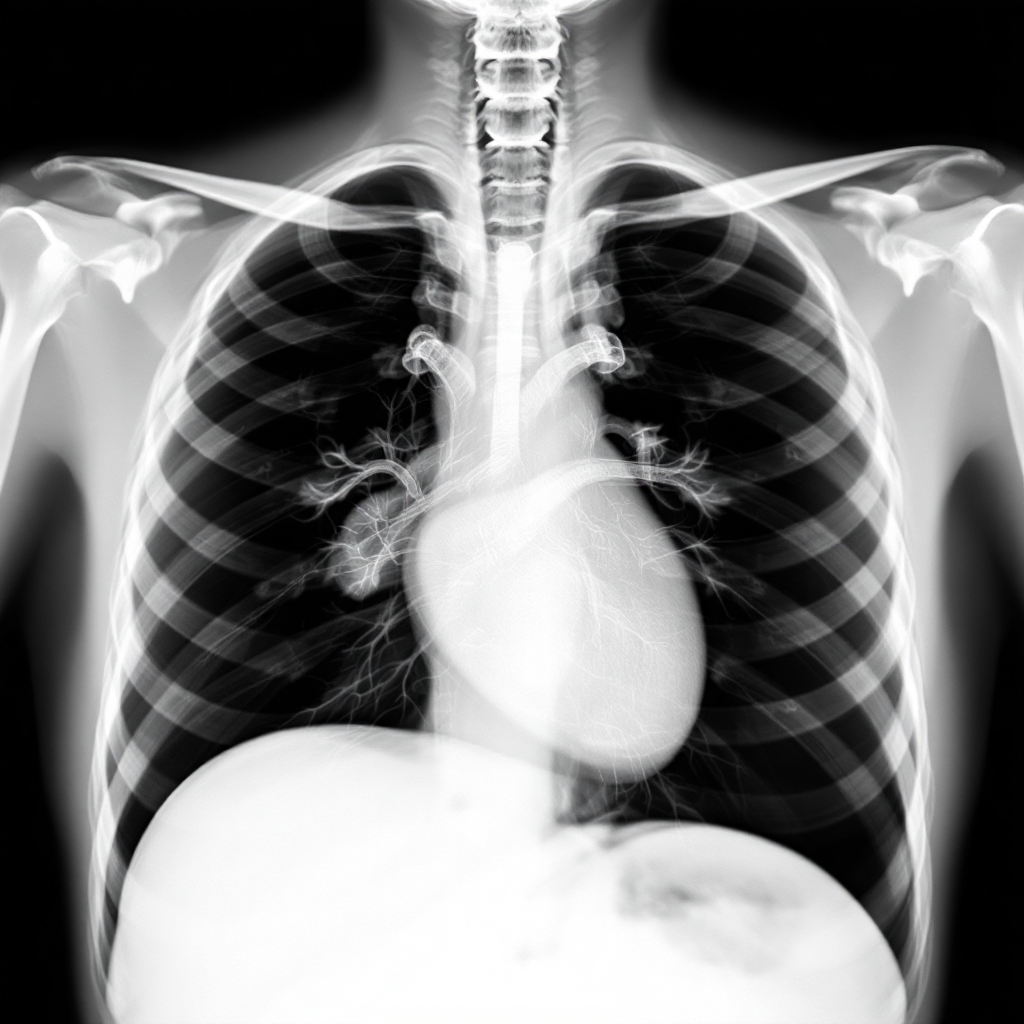

촬영 자세가 가장 중요한 부분이에요. PA 촬영에서는 가슴을 X-ray 카세트(필름판)에 밀착시키고 서게 되어요. 이때 턱을 살짝 들어서 목뼈가 폐와 겹치지 않도록 하고, 양손은 허리에 올려놓거나 머리 위로 올리는 자세를 취하게 돼요. 어깨는 자연스럽게 내리고, 등을 곧게 펴는 것이 중요해요. 처음에는 어색할 수 있지만 기사분이 자세히 설명해 주시니까 걱정 안 하셔도 돼요.

호흡 조절도 매우 중요한 부분이에요. X-ray를 조사하는 순간에는 숨을 깊게 들이마시고 참아야 해요. 보통 '크게 숨을 들이마시고 참으세요'라는 안내가 나오면 최대한 깊게 숨을 들이마신 후 잠시 멈춰 있어야 해요. 이렇게 해야 폐가 최대한 펼쳐져서 폐의 모든 부위를 선명하게 관찰할 수 있거든요. 숨을 참는 시간은 보통 3-5초 정도로 짧으니까 너무 부담스러워하지 마세요.